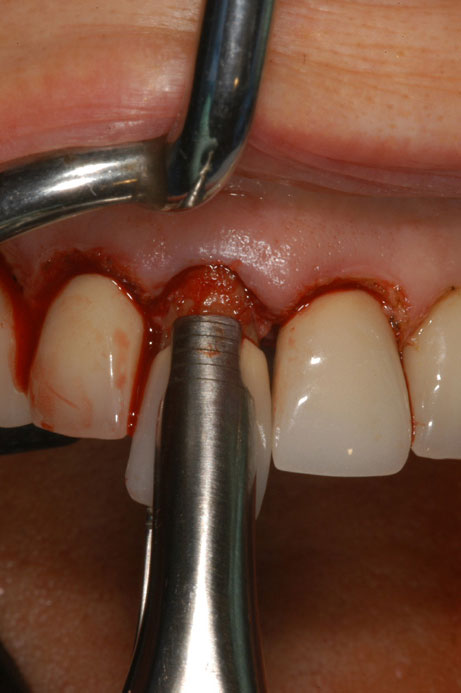

A dental implant most closely replicates natural tooth structure. Once it is osseointegrated, many patients cannot differentiate an implant from a natural tooth. Furthermore, dental implants do not decay or need root canal therapy. Even though the cost is slightly more than a bridge, it is an investment for the future, as implants usually last longer than a bridge. A 10-year report on posterior single implants shows a success rate of 97%.33 Once an implant is placed, the osseointegration and tissue healing time of approximately 4 months is necessary before a final crown is placed. A temporary crown can be placed the same day the implant is placed, but this is only for esthetics, not for function (Figure 15 through Figure 19).

Figure 15 – Extraction of anterior tooth No. 8 without detaching the gingiva.

Figure 15